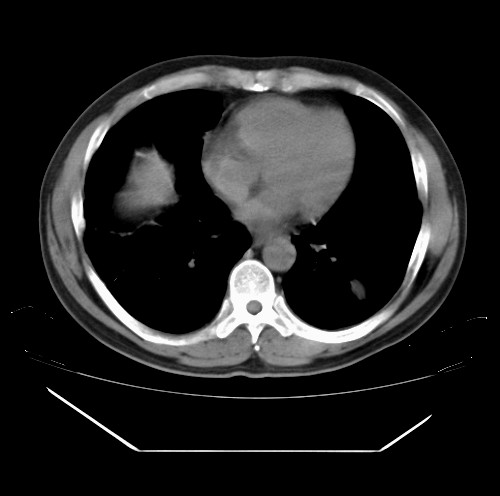

标题: CT22085:双肺多发结节

男,44岁,咳嗽,痰中带血2天。

病灶大部分位于胸膜下,结节大小相差不是很大,肺尖太干净。这种结核没见过,我认为可排除。

首先考虑转移,不除外肉芽肿、真菌感染。建议查其它。

除肺内及胸膜下可见多发大结节外,在肺小叶中心核、小叶间隔及支气管血管束上亦可见多方小结节,可以认为是随机分布。考虑转移可能性大。

仔细观察病灶形态,病灶边界部分清楚,结合临床症状,首先考虑转移,纵隔内多个肿大淋巴结影。

双肺血管纹理末端多发类圆形结节,边界光滑清晰 气管前腔静脉后淋巴结肿大

考虑转移瘤

沿血管分布,位于血管末端。转移瘤多见,血行性菌栓也可见到。

本例双肺多发类圆形高密度灶,边清,结合病史多考虑双肺多发转移改变,可以结合实验室检查。